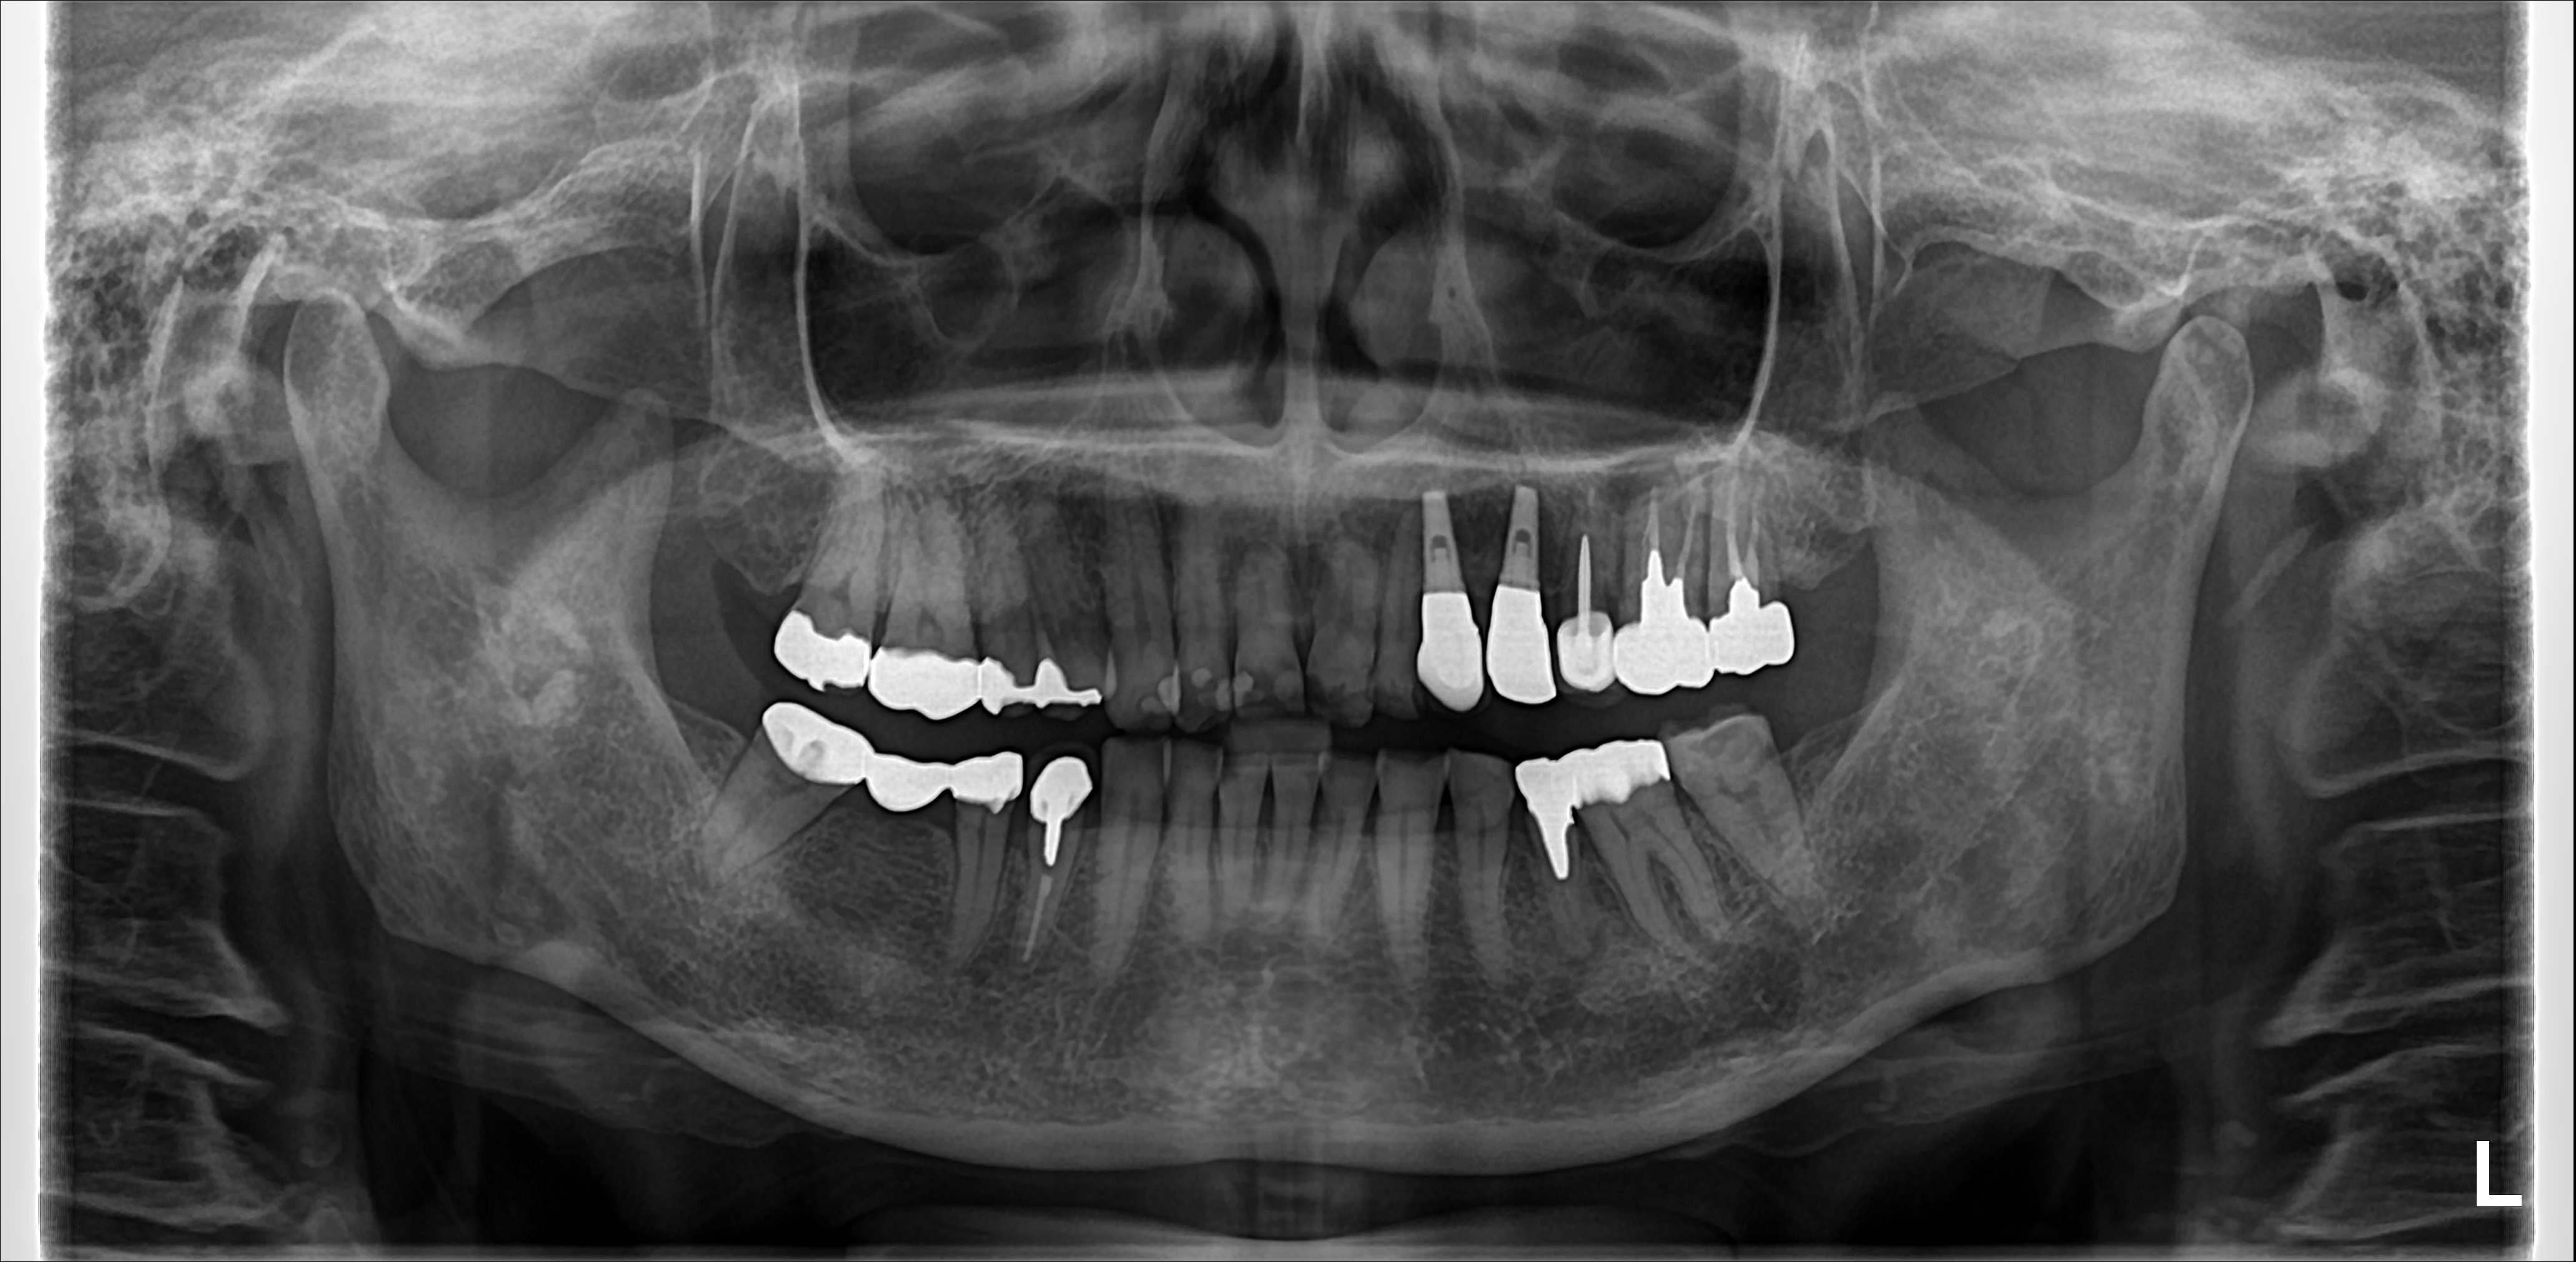

インプラント希望の患者さん。

インプラントを希望して来院された、ある方のパノラマX線写真です。左下7番の歯根が割れています。驚いたことに定期的に通院していた歯科医院では1年以上もこの状態だったそうです。もっと早く抜歯すべきでした。...